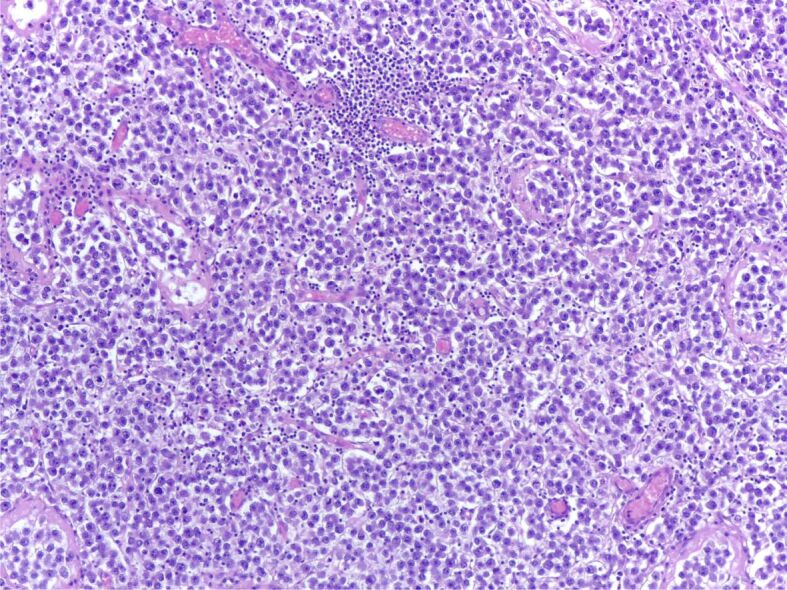

Abstract Image